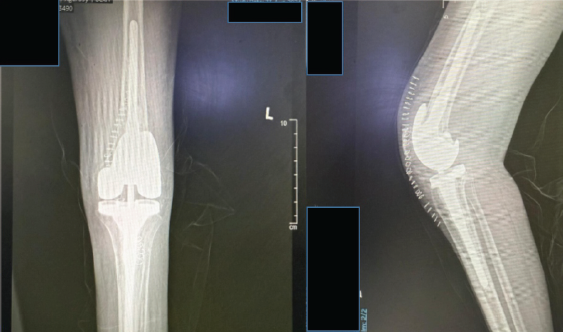

- August 21, 2024: Left total knee replacement (Fig. 5)

Figure 5: Post-operative X-ray showing the left total knee replacement (August 23, 2024).